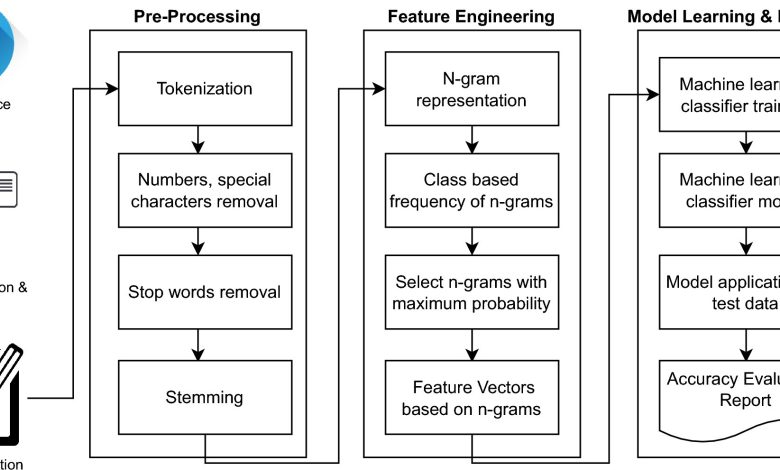

Metodologia proposta. Crédito: Relatórios científicos (2024). DOI: 10.1038/s41598-024-69687-8

Cientistas analisaram milhões de tuítes para identificar sobreviventes da COVID-19 que vivem com transtorno de estresse pós-traumático (TEPT), demonstrando a eficácia do uso de dados de mídia social como uma ferramenta para triagem e intervenção precoces.

Os pesquisadores construíram um conjunto de dados de 3,96 milhões de postagens no Twitter, agora conhecido como X, de usuários que mencionaram em sua linha do tempo que testaram positivo para COVID em algum momento entre março de 2020 e novembro de 2021.

Usando classificadores de aprendizado de máquina, incluindo Support Vector Machine (SVM), Naïve Bayes, K-Nearest Neighbor e Random Forest, a equipe classificou as postagens como positivas ou negativas para TEPT, alcançando uma precisão de 83,29% usando SVM.

Ao analisar os tweets, os cientistas identificaram a infecção pela COVID-19 como um evento desencadeador. Eles então procuraram sintomas sob fatores-chave, incluindo revivência, hiperexcitação e comportamento de evitação, buscando uma variedade de palavras-chave, incluindo:

- Flashbacks, pesadelos, intrusões, pânico, sonhos vívidos (revivência)

- Agitado, assustado, hipervigilante, irritável (hiperarousal)

- Evitar, evitação (comportamento de evitação)

- Ansiedade, depressão, pensamentos suicidas, apetite, trauma, fadiga (outros sintomas)

Tweets que tinham tanto o status de COVID-19 quanto uma das palavras-chave de TEPT foram considerados “Positivos para TEPT”. Tweets que mencionavam palavras-chave de TEPT, mas em relação a outros eventos que não a COVID-19, foram considerados “Negativos para TEPT”.